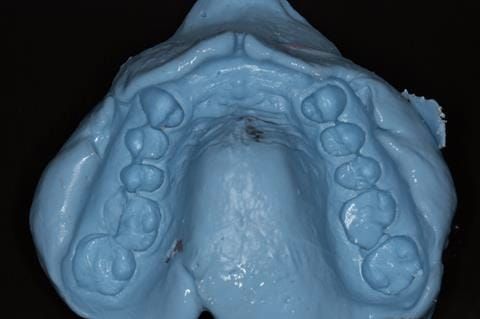

- Extract the upper 2-2 teeth and replace with an interim acrylic based partial denture. Reline the interim denture over 9 - 12 months, replacing with a definitive cobalt chromium based partial denture. The definitive denture would ideally be designed as an occlusal protective splint to reduce the the potential for mechanical wear and breakages of the moderately/heavily restored maxillary dentition. In addition, should further upper teeth require extraction they could be added on to the denture cobalt chromium framework - therefore a new prosthesis would not be required as future teeth are lost. This option would produce an excellent aesthetic outcome. This is the option the patient chose to have.

Following consultation and second discussion appointment the patient chose to have option 3 namely, a maxillary cobalt chromium based partial denture/protective occlusal splint. The clinical situation and treatment process is shown in detail below with photographs. The patient was successfully rehabilitated with this and her quality of life considerably improved. The clinical work was provided by Finlay and the technical work by Rowan.